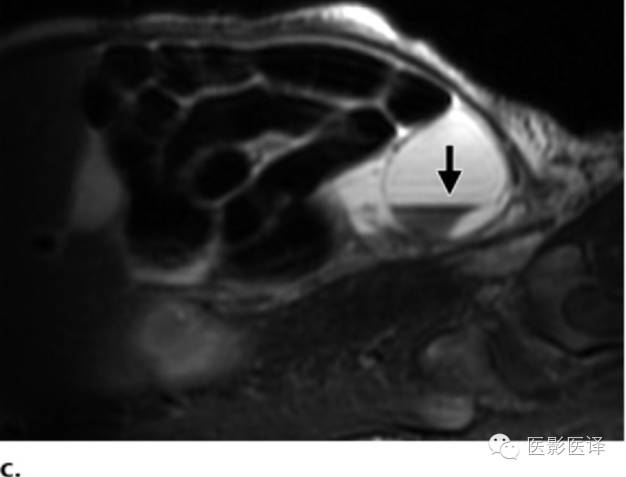

图7 囊肿中的液液平面。(a)轴位胎儿超声图像显示在左肾(LK)前方一个孤立性囊性肿块(箭),脊柱(Sp)另一侧可以看到正常的右肾(RK),三周后的随访图像(未展示)显示团块中出现液液平面。(b)新生儿经腹长轴位图像显示一个薄壁囊性团块,有液液平面(箭),子囊(箭头)是卵巢囊肿的确诊征象。(c)新生儿矢状位T2WI显示一个出血性卵巢囊肿,有液液平面(箭)和低信号血液成分。

MR成像评估的作用